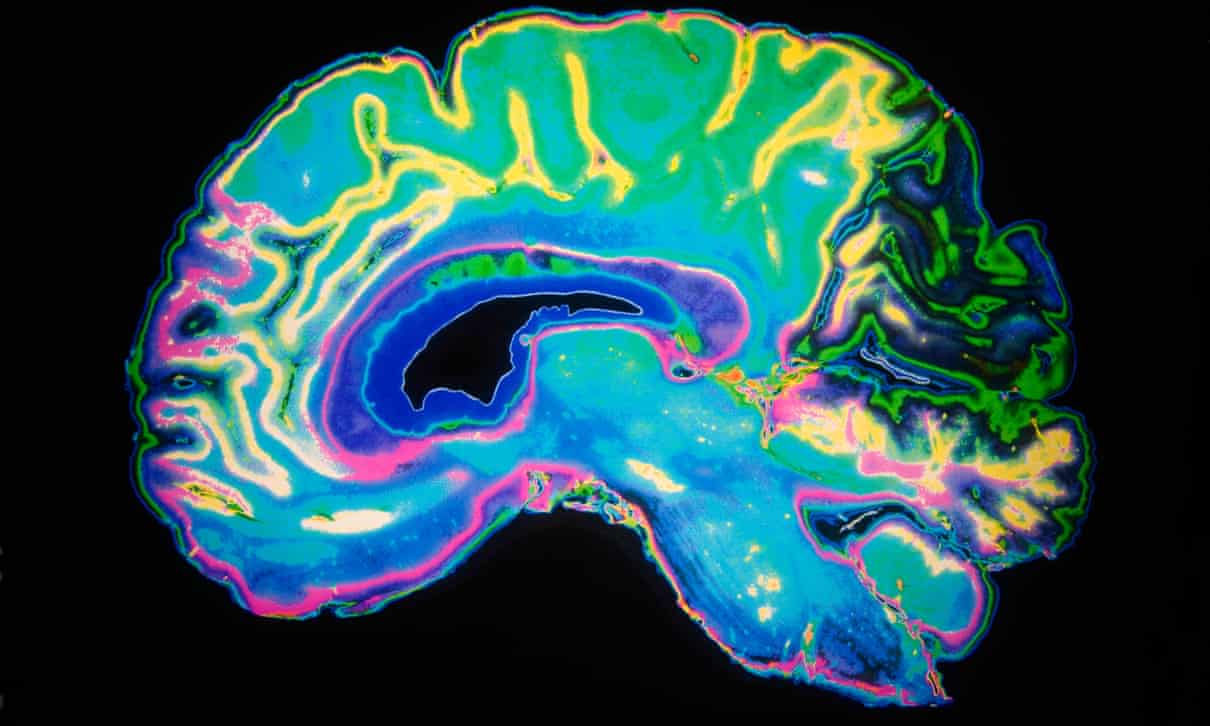

მეცნიერები – იმ პაციენტებშიც კი, რომლებიც Covid–19–სგან განიკურნენ, ტვინის მძიმე დაზიანებები გამოვლინდა

იმ პაციენტებშიც კი, რომლებიც Covid–19–სგან განიკურნენ ან დაავადების მსუბუქი ფორმები აღენიშნებოდათ, ტვინის მძიმე დაზიანებები გამოვლინდა, – ამის შესახებ ნათქვამია ბრიტანელი მეცნიერების ანგარიშში, რომელიც დღეს ჟურნალ "Brain"–ში გამოქვეყნდა.

ნევროლოგების თქმით, ქვეყნის მასშტაბით შეისწავლეს 40 კოვიდ–ინფიცირებული პაციენტი, რომელთაც გამოუვლინდათ ტვინის გართულებები, მათ შორის – თავის ტვინის ანთება, დელიმიუმი და ინსულტი.

10 პაციენტს ცენტრალური ნერვული სისტემის ანთება გამოუვლინდა, 10 პაციენტს – ტვინის დაავადება დელირიუმი ან ფსიქოზი, 8 პაციენტს – ინსულტი, დანარჩენს კი – გილინ-ბარის სინდრომი, რომელიც დამბლას იწვევს. 40 შემთხვევიდან 5% ფატალური შედეგით დასრულდა.

კვლევის შედეგების თანახმად, Covid-19–სგან განკურნებული პაციენტების ნაწილს სუნთქვის პრობლემები და დაღლილობის შეგრძნება, ზოგიერთს კი დაბუჟება, სისუსტე და მეხსიერების პრობლემები დიდი ხნის განმავლობაში დაუტოვა.

"ჩვენ ვხედავთ, რომ Covid-19 აზიანებს ტვინს ისე, რაც ადრე არც ერთი სხვა ვირუსის დროს არ გვინახავს”, - განაცხადა კვლევის ერთ–ერთმა ავტორმა University College London Hospitals NHS–ის მეცნიერმა მაიკლ ზანდიმ.